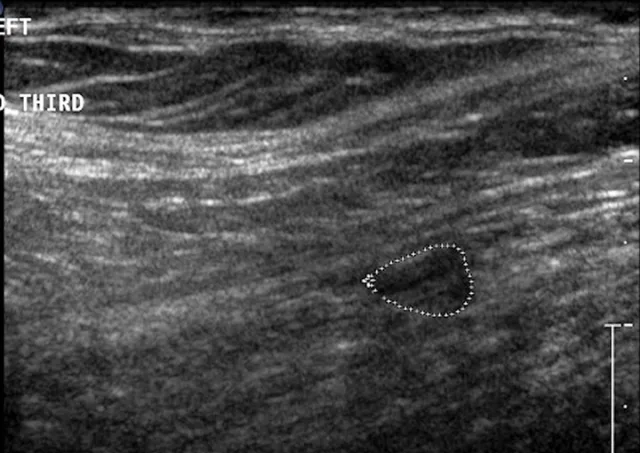

Biceps tenosynovitis is a common cause of forelimb lameness that most frequently affects medium- and large-breed dogs secondary to repetitive fatigue. It is characterized by inflammation of the biceps brachii tendon and the synovial sheath that envelops it in the shoulder joint (Figure 1).1,2 Clinical presentation often consists of a chronic progressive forelimb lameness that is worsened by exercise. The severity of lameness can vary from mild to nonweight-bearing, and atrophy of the supraspinatus and infraspinatus muscles is often present (Figure 2). Pain may be elicited during the biceps test, in which pressure is applied on the biceps tendon in the intertubercular groove when the shoulder is flexed and the elbow extended (Figure 3).1,2 Additional diagnostics (eg, ultrasonography, MRI, arthroscopy) are often needed to confirm diagnosis.1-3 Medical management (eg, rest, NSAIDs, physiotherapy) often results in resolution of mild lesions.1-3 Some dogs may require biceps tendon release or tenodesis to resolve pain and lameness.1-3

FIGURE 5

Ventrodorsal radiographic projection of a 9-year-old dog with right hindlimb lameness and hip pain. In addition to bilateral hip dysplasia and secondary osteoarthritis, mineralization is present within the right iliopsoas muscle near the tendon insertion on the lesser trochanter (arrowhead), which indicates a chronic strain injury.